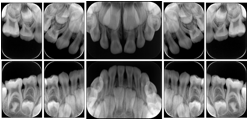

3. A dental provider wishes to capture a series of DICOM IO images for the patient’s dentition. The tooth morphology, teeth are divided into molars, premolars, canines and incisors, and a number of images for each jaw. The anatomic information was captured utilizing the triplet of schema. This standard code sequence is based on ISO 3950-2010, Dentistry - Designation system for teeth and areas of the oral cavity.

Every IO image should have anatomic information either through the primary or modifier sequence.

In most standard cases, images are oriented in structured layouts. These structured displays are useful to be shared between providers for reference purposes.

Table OO.1.1-1 shows structured display standard templates, where Viewset ID is based on the Japanese Society for Oral and Maxillofacial Radiology (JSOMR) classification provided by JIRA (Japan Medical Imaging and Radiological Systems Industries Association, www.jira-net.or.jp). Expected or typical teeth to be imaged location, region and designation codes are based on ISO 3950-2010, Dentistry - Designation system for teeth and areas of the oral cavity. For all the hanging protocols listed in OO.1.1-1, the value to use for Hanging Protocol Creator (0072,0008) is "JSOMR" and the value to use for Hanging Protocol Name (0072,0002) does not include "JSOMR" (e.g., "DL-S001A", not "JSOMR DL-S001A").